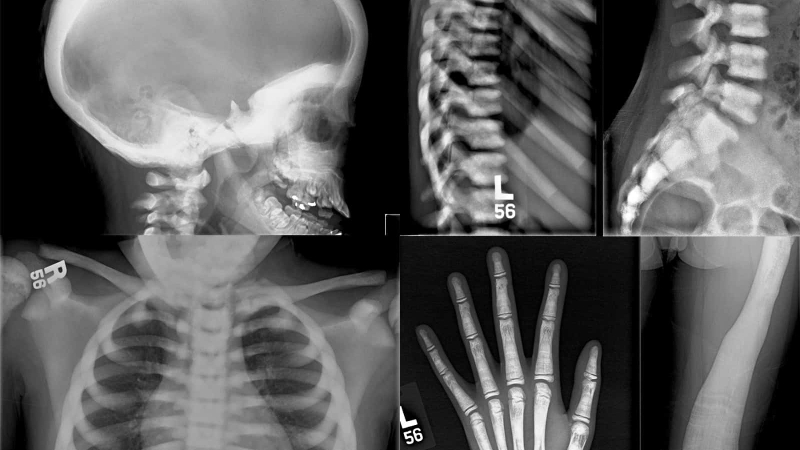

Bệnh xương hóa đá là căn bệnh về xương rất hiếm gặp với tỉ lệ mắc phải là 1/200.000 người. Đây là căn bệnh có tính chất di truyền với đặc điểm là mật độ xương tăng và có sự bất thường ở hình thể xương.

Trẻ em và người trưởng thành đều trải qua hai quá trình là phá hủy và tái tạo xương. Trong quá trình phá hủy xương, do khả năng hấp thu xương của tế bào hủy cốt mất đi khiến cho hoạt động tái tạo xương chiếm ưu thế và tạo điều kiện thuận lợi cho xương hóa đá xuất hiện.

Hiện nay, bệnh xương hóa đá được xác nhận có 70% nguyên nhân do di truyền, do khiếm khuyết bẩm sinh trên gen dẫn đến hoạt động bất thường của các tế bào hủy cốt. Khi các tế bào này bị lỗi và không làm việc thì xương cũ sẽ không được hủy đi mà xương mới vẫn tiếp tục hình thành dẫn đến mật độ xương tăng cao và hình thành bệnh.